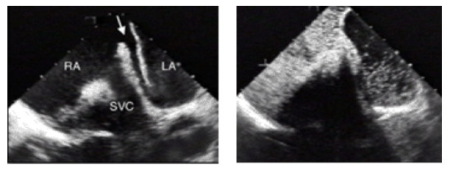

Ist der Bubble-Test positiv, führt der Weg unweigerlich zum Kardiologen, denn jetzt sollte man den Befund mit einer bildgebenden Diagnostik genauer untersuchen und quantifizieren. Das gelingt mit einer sogenannten "transösophagealen Echokardiographie" (engl.: transesophageal echocardiography, abgekürzt TEE). Damit kann man durch ein in die Speiseröhre (Ösophagus) eingeführtes Endoskop mit eingebautem Schallkopf insbesondere Erkrankungen der Vorhöfe diagnostizieren, da die Speiseröhre in unmittelbarer Nachbarschaft zum Herzen liegt. Deshalb nennt man diese Untersuchung auch landläufig ein "Schluck-Echo". Das hört sich schlimmer an als es in der Praxis ist. Während der Untersuchung wird, wie beim Bubble-Test, ein Kontrastmittel appliziert und der Übertritt vom rechten in den linken Vorhof dargestellt. Die Passage von Echokontrast (sog. "Bubbles") vom rechten in den linken Vorhof innerhalb von drei bis sechs Herzzyklen ist dabei diagnostisch für ein PFO. Ein TEE stellt die Methode der Wahl dar und ermöglicht eine genaue Größenbestimmung des PFO und quantifiziert das Ausmaß des Shunts.

Oben links und rechts: Der Pfeil zeigt den offenen Kanal eines PFOs zwischen dem rechten Herzvorhof (RA = right atrium) und dem linken Herzvorhof (LA = left atrium). Die "Tür ist hier mehr als nur angelehnt" – sie steht sogar etwas offen.

Der weiße Fleck im rechten Vorhof und die Bezeichnung SVC (suprior vena cava) bezieht sich auf die obere Hohlvene, die dort in den rechten Vorhof eintritt. Der Vergleich der weißen Punkte (Bubbles) zwischen dem linken und dem rechten Bild zeigt deutlich den Übertritt von Bubbles. Der linke Vorhof ist nach Kontrastmittelgabe sozusagen voller weißer Punkte.